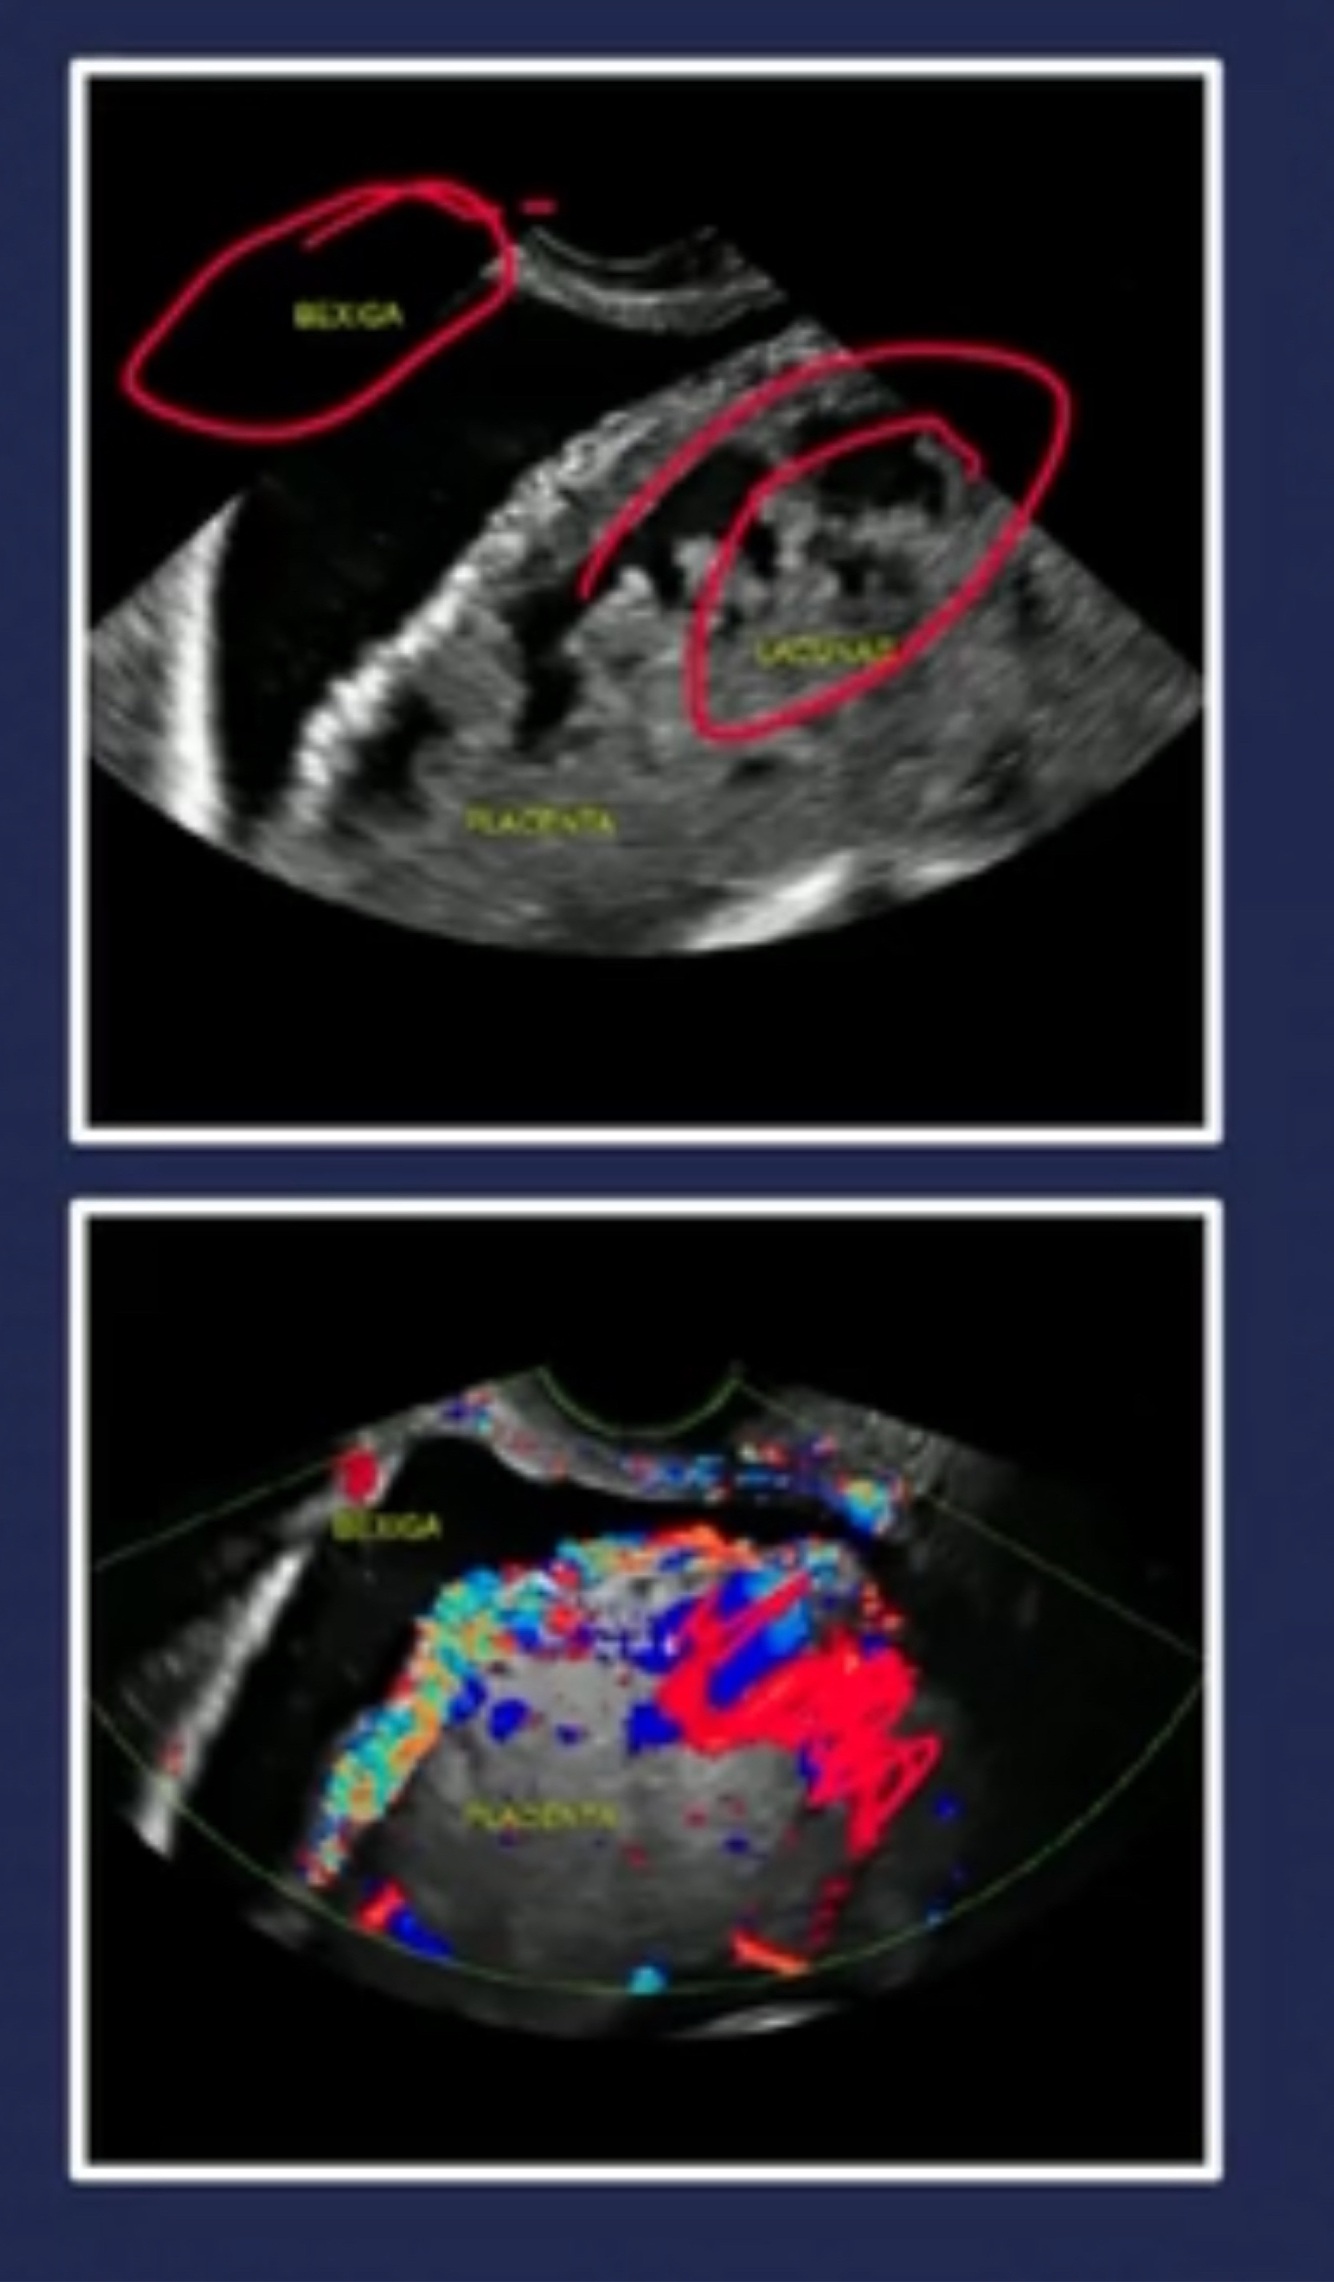

Sinal USG mais especifico de placenta acreta?

Presenca de Lacunas vasculares na placenta